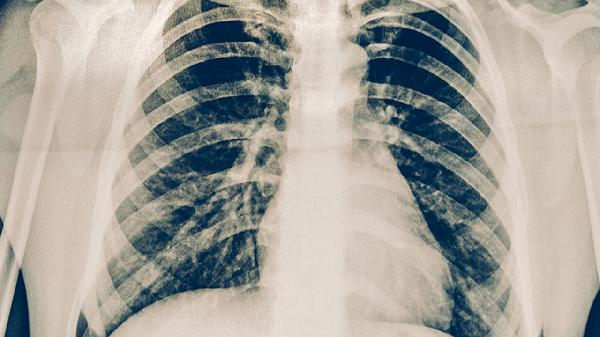

治疗决策需结合胸部X线、炎症指标CRP、PCT及病原学检查。支原体肺炎首选大环内酯类口服,而细菌性肺炎伴菌血症才需静脉用药。临床改善后应尽早转换为序贯口服治疗。